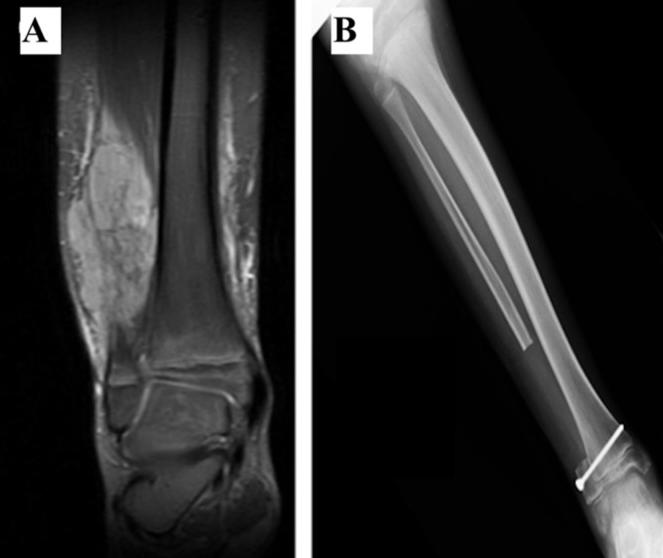

Side-by-side x-ray images. The left image is a close up of a fibula with a large tumor and the x-ray image itself is in shades of dark grey. The right image shows a lower leg with no tumor; the x-ray image is lighter grey and white compared to the left image.

MRI scans showing a large Ewing sarcoma tumor in the fibula of a 10-year-old boy (A) and the lower leg after surgery to remove the tumor (B).

Credit: Curr Oncol. Oct 2021. DOI: 10.3390/curroncol28050299. CC BY 4.0.